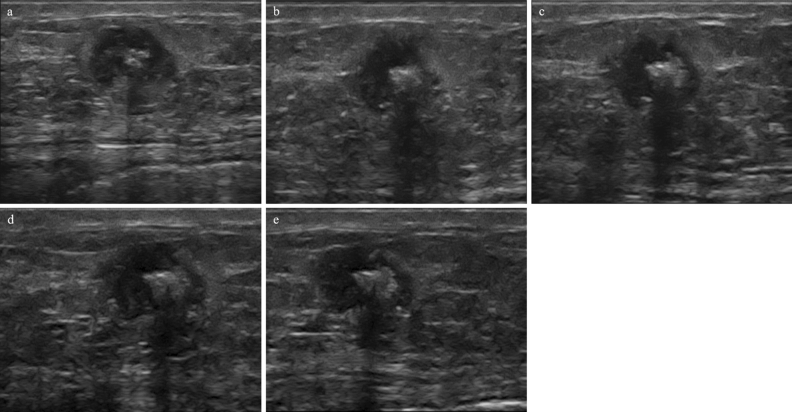

Examples of B-mode images for the case N-RT (RMC = 100%) and RT (RMC = 0) are shown in Figs. 2 and 3, respectively.

Figure 3.

Ultrasound results from a 65-year-old patient with breast cancer (carcinoma invasivum apocrinale, Grade 3, TNBC, Ki 67–20%). In B-mode examination before treatment (a) the tumour was hypoechoic with calcification. After the first (b), second (c), third (d), and fourth (e) course of the NAC, echogenicity remains unaltered (histopathological verification: N-RT, RMC = 100%).